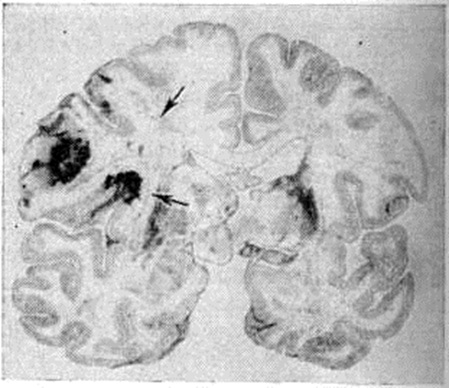

Геморрагический инсульт, как правило, возникает при заболеваниях, протекающих с повышенным артериальное давление. Это обусловлено тем, что сосудистые кризы (смотри полный свод знаний), характерные для гипертонической болезни (смотри полный свод знаний) и артериальной гипертензии (смотри полный свод знаний Гипертензия артериальная), приводят к морфологический изменениям стенок внутримозговых сосудов с нарушением их проницаемости — плазматическому пропитыванию (рисунок 1), некрозам (рисунок 2), образованию микроаневризм (рисунок 3) и их разрывам. Разрыв врождённых артериальных и артериовенозных аневризм может протекать на фоне нормального давления. Преимущественная локализация и характер геморрагий определяются особенностями ангиоархитектоники различных отделов мозга. При гипертонической болезни наиболее тяжёлым изменениям подвергаются сосуды подкорковых узлов и зрительного бугра. Это объясняется отхождением глубоких ветвей под прямым углом от средней мозговой артерии, являющейся продолжением внутренней сонной артерии, и незначительным числом анастомозов сосудов в этой области. В связи с этим на вскрытии кровоизлияния наиболее часто (40%) обнаруживаются в подкорковых узлах с распространением в прилежащее белое вещество (так называемый латеральные кровоизлияния, то есть расположенные латерально от внутренней капсулы, рисунок 4). Второе место по частоте (16%) занимают обширные кровоизлияния, разрушающие подкорковые узлы, внутреннюю капсулу, зрительный бугор (так называемый смешанные кровоизлияния — рисунок 5). Кровоизлияния в зрительный бугор (так называемый медиальные — рисунок 6) составляют 10%, в мозжечок — 6—10%, в мост мозга — 5% от общего числа внутримозговых геморрагий. Кровоизлияния только в белое вещество полушарий мозга встречаются крайне редко. Подразделение полушарных кровоизлияний на латеральные, медиальные и смешанные имеет особое значение в связи с хирургическим лечением геморрагического Инсульт.

Кровоизлияния типа геморрагического пропитывания возникают преимущественно в зрительных буграх, реже в мосту мозга и составляют 15% внутримозговых кровоизлияний. Они являются результатом слияния мелких очагов кровоизлияний, возникающих путём диапедеза из мелких сосудов, имеют вид очагов красного цвета, дряблой консистенции и в силу внешнего сходства иногда напоминают геморрагический инфаркт. В первые часы Инсульт нарушается проницаемость сосудов на границе с кровоизлиянием, развивается отёк; кровь распространяется по ходу нервных волокон. К концу первых суток наблюдаются лейкостазы и лейкодиапедез, размеры очага увеличиваются за счёт диапедезных геморрагий и некробиотических изменений в отёчном веществе мозга. Через двое суток начинается процесс репарации — появление зернистых шаров и гипертрофированных астроцитов; позже образуется вал из астроглии и новообразованных сосудов, кровь подвергается гемолизу, появляются макрофаги с гемосидерином, образуются аргирофильные и коллагеновые волокна. Исходом кровоизлияния может быть формирование глиомезодермального рубца или кисты, содержащих гемосидерин (рисунок 9). В 80—85% кровоизлияний на вскрытии выявляется прорыв крови в желудочки, значительно реже — в подпаутинное пространство. В последнее кровь может также проникнуть из четвёртого желудочка. Первичные вентрикулярные геморрагии нетравматического генеза — явление казуистическое. При разрыве врождённых аневризм артерий основания мозга возникают первичные субарахноидальные кровоизлияния, которые обычно локализуются на базальной поверхности или в латеральной борозде; иногда кровь проникает в субдуральное пространство; часто повреждается вещество мозга (субарахноидально-паренхиматозные кровоизлияния). Расположение гематом, образующихся при этом, зависит от локализации аневризмы, обычно это базальный отдел лобной доли или височная область. В части случаев при незначительном субарахноидально-паренхиматозном кровоизлиянии возможен массивный прорыв крови в желудочки (рисунок 10), что иногда ошибочно диагностируется как первичное вентрикулярное кровоизлияние.